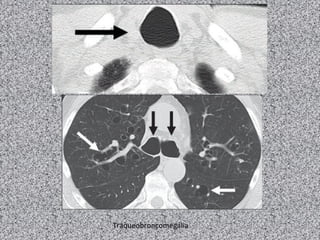

Anomalias congênitas da via aérea:

Traqueobroncomegalia